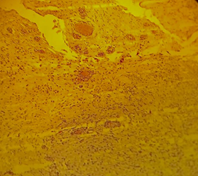

Se realizo biopsia excisional, la misma que muestra hallazgos macroscópicos: Fragmento irregular de tejido blando de 0.9 x 0.5 cm, presencia de una lesión nodular delimitada al corte es de aspecto quístico. (Fig. 2)

Histológicamente existen dos tipos de mucocele: Extravasación y Retención. El mucocele de extravasación es el resultado de la ruptura de un ducto de la glándula salival como consecuencia de un traumatismo, tornillos ortodónticos o hábitos parafuncionales (17-19), la misma que genera una extravasación de contenido liquido sobre el tejido conectivo generando así la lesión principalmente en pacientes jóvenes en las primeras dos décadas de vida, mientras el mucocele de retención es una lesión poco frecuente y se da por un bloqueo de los ductos de la glándula salival la misma que genera retención de secreción salival(20-21). More y Cols (22) señala que “El mucocele de extravasación presenta mayor prevalencia en pacientes jóvenes con una localización común en el labio inferior (36.2%) con mayor frecuencia en pacientes hombres” mientras Hayashida y Cols (23) manifiesta que “El mucocele de retención presenta mayor prevalencia en pacientes desde la segunda década de vida y con mayor frecuencia en mujeres 60.12%”, pero coinciden con la localización más frecuente en el labio inferior.